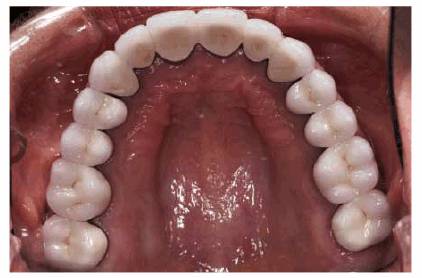

patient (Figures 17-1A to

C

Figure 17-1A to C: These photographs illustrate the complex dental condition of a 71-year-old male: (A) The palatal cervical regions of the maxillary anterior teeth exhibit sharp, wedge-like lesions that are characteristic of abfraction. These areas would be difficult, if not impossible, to have resulted from toothbrush abrasion. (B) The buccal aspects of the maxillary posterior teeth show smooth, concave configurations that are consistent with toothbrush abrasion and/or erosion. (C) The buccal surfaces of the mandibular teeth have lesions that possess components of both abfraction (sharp margins in the occlusal regions) and abrasion (concave geometry and gingival recession in the cervical regions).